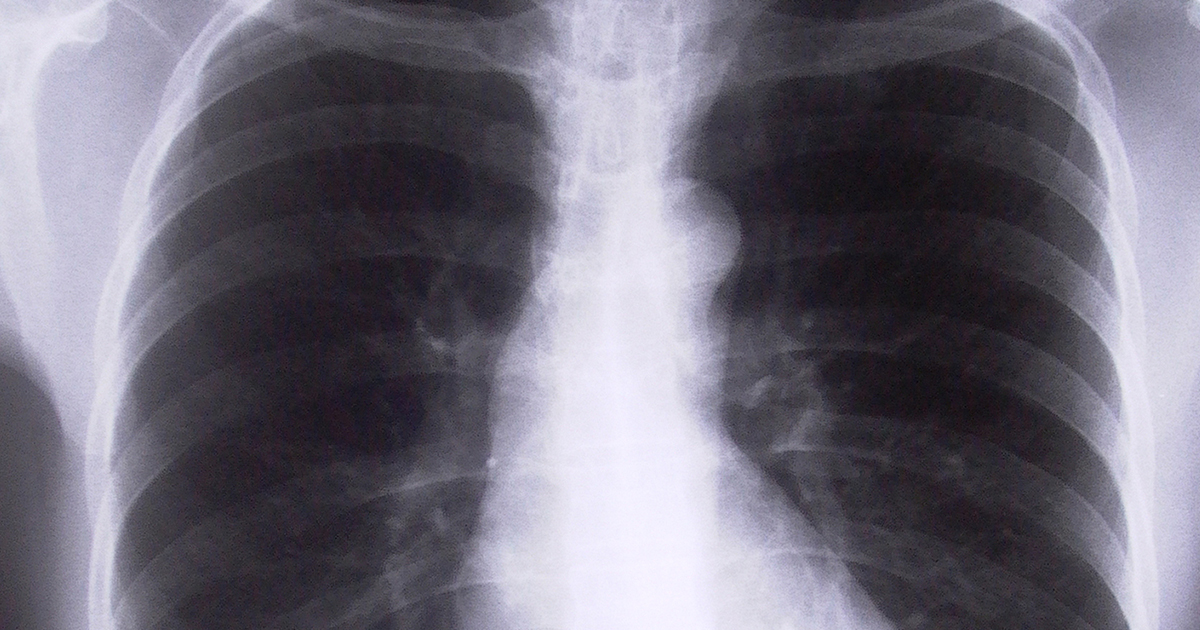

The worker, (who for confidentiality reasons, we will call ‘B’) suffered a crush injury to his upper body in 1999. In 2014, he collapsed at home and was hospitalised and a pacemaker was inserted into his chest. The pacemaker caused an infection of the heart muscle because the pacing wire was pushed too far in. The pacemaker lead was replaced in 2017, and a further claim for the costs of that surgery were made and rejected by the compensating authority. The claim was based on damage to the heart having been caused in 1999 by a “hydraulic compression” of a node within the heart.

The SAET found that despite a competing theory being advanced by a specialist clinical cardiologist that the need for the pacemaker was unrelated to the 1999 injury, B still succeeded. The Judge accepted evidence from another cardiologist that the crush injury would likely have damaged the heart; that the need for the pacemaker was because of that damage; and that the lack of any evidence from a treating doctor did not mean the claim failed.